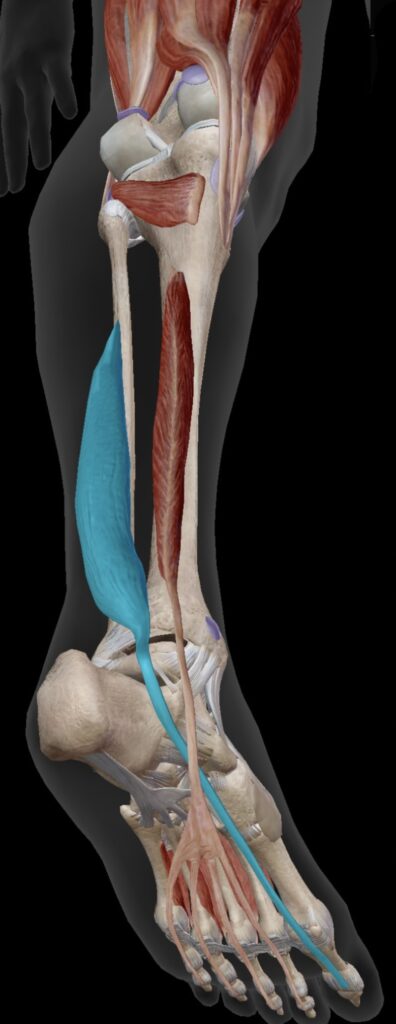

安定したルルベを支えるには、親指をコントロールする長母趾屈筋、親指以外をコントロールするの長趾屈筋などの足の指を動かす、地面を掴む筋肉も大事です。

この筋肉は足首の内くるぶしの後ろを通っており、ここがしっかり機能すると、足首を内側から支えるサポーターの役割をになってくれます。